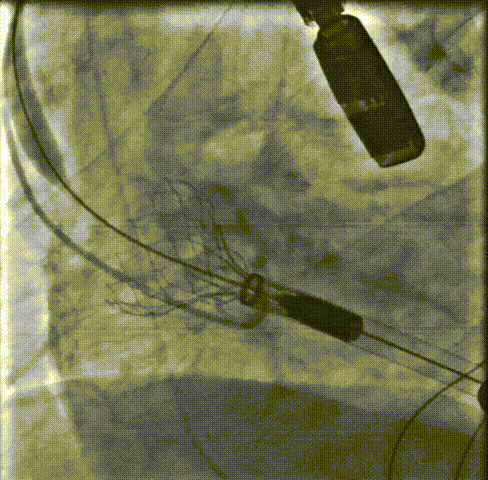

主动脉根部造影:主动脉根部造影可见主动脉瓣运动受限,伴有明显反流,瓣环平面上下可见大量团块状钙化。重度横位心。

预扩张:22mm球囊预扩后,患者出现室颤,电复律后转为窦性。

释放支撑臂:0位匀速释放Xcor-26瓣膜流出端。

瓣膜释放前根部造影瓣膜打开到80%,再次行主动脉根部造影,支架高度和植入深度满意,不需要回收,直接释放瓣膜。

释放瓣膜:0位匀速释放Xcor-26瓣膜流入端。

后扩张:22mm球囊后扩张,支架膨胀形态良好,未见支架回弹,未见移位。

术后造影:最终主动脉根部造影示支架瓣膜释放位置佳,瓣叶运动良好,支架内未见明显反流,轻度瓣周漏。